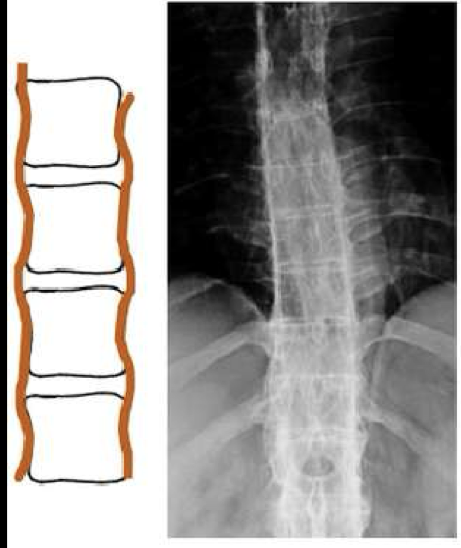

What finding of AS is found in this image

symmetrical, thin, marginal syndesmophytes (bamboo sign)

gracile/fragile

Where should you be looking every time you think the disease could be AS

SI joints